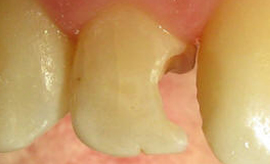

KONZERVATIVA - KOMPOZITNE ZALIVKE ![]()

Kompozitna zalivka nadomešča izgubljeno zobno strukturo (zaradi kariesa ali loma), v primerih, ko okvara na zobu ni prevelika. V preteklosti so se uporabljali neestetski materiali, kot je amalgam. Danes se amalgam skoraj ne uporablja več zaradi slabe vezi z zobom in »kovinskega« nenaravnega videza. Kompozitni materiali, ki jih uporabljamo danes, so estetski, imajo odlične mehanske lastnosti in se dobro vežejo na strukturo zob (če se uporablja pravilno).

Za zdravljenje majhnih, površinskih kariesov, popravilo majhnih defektov in nepravilnosti ter popravilo manjših estetskih nepravilnosti v obliki in barvi zob uporabljamo najmanj invazivne metode odstranjevanja kariesa s posebnimi svedri za minimalno invazivno preparacijo, ki izbrusi le karies ali odstrani staro plombo, zdrava zobovina pa ostane nedotaknjena. Takšni posegi so praviloma neboleči tudi brez anestezije. Kadar pa gre za obsežnejši karies, zlom zoba ali menjavo večje plombe nujna je obsežnejša preparacija ter bolj zapletene tehnike izdelave plomb. Pri tem uporabljamo najnovejše nadstandardne plombirne materiale, saj imajo vrsto prednosti pred klasičnimi zalivkami. So izredno obstojni, estetski ter prijazni zdravju in okolju.

Kompozitne zalivke se izdelujejo tako, da zvesto posnemajo videz naravnih zob. To pomeni, da se s pomočjo kompozitnega materiala oblikuje vsaka jamica in vršek, ki jih ima naravni zob, prehod med zobmi in zalivko pa mora biti neopazen. Na modeliranju jamiv in vrškov ne vztrajamo samo zaradi estetike, temveč tudi zaradi funkcionalnih razlogov. Vsaka zalivka ali krona z razlogom natančno posnema videz naravnih zob. Če tega ne bi upoštevali, bi prišlo do motnje pri naravni razporeditvi sil pri vgrizu, kar lahko povzroči resne zaplete v ustni votlini (izraščanje nasprotnega zoba, če je zalivka prenizka, zatikanje hrane med zobmi in krvavitev dlesni, slab zadah in nastanek žepov).